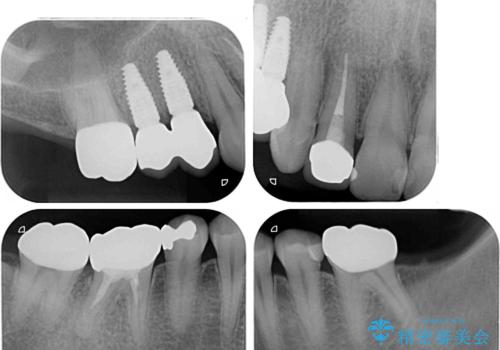

レントゲン写真などで診査した結果、奥歯の銀歯の下にはむし歯が多く存在し、右上の奥歯は歯根が破折していました。

破折した歯を抜去し、インプラントによる補綴を行うこととしました。